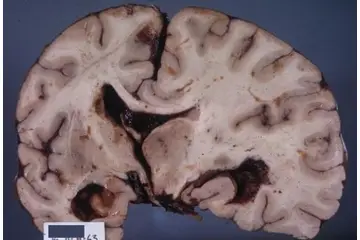

Beyinde kitle ameliyatı, genellikle tümörler, kist veya diğer anormal oluşumların cerrahi olarak çıkarılması amacıyla yapılan bir işlemdir. Bu tür bir ameliyat, beyin dokusuna doğrudan müdahale gerektiği için belirli riskler taşır ve sonrasında hastalar için çeşitli zorluklar ortaya çıkabilir. İşte bu makalede, beyin kitle ameliyatının riskleri ve sonrası hakkında detaylı bir inceleme yapılacaktır. 1. Beyin Kitle Ameliyatının Riskleri Beyin kitle ameliyatı, birçok risk barındırır. Bu riskler arasında şunlar bulunmaktadır:

4. Potansiyel Komplikasyonlar Ameliyat sonrası komplikasyonlar, hastanın genel sağlığını etkileyebilir. Bunlar arasında: